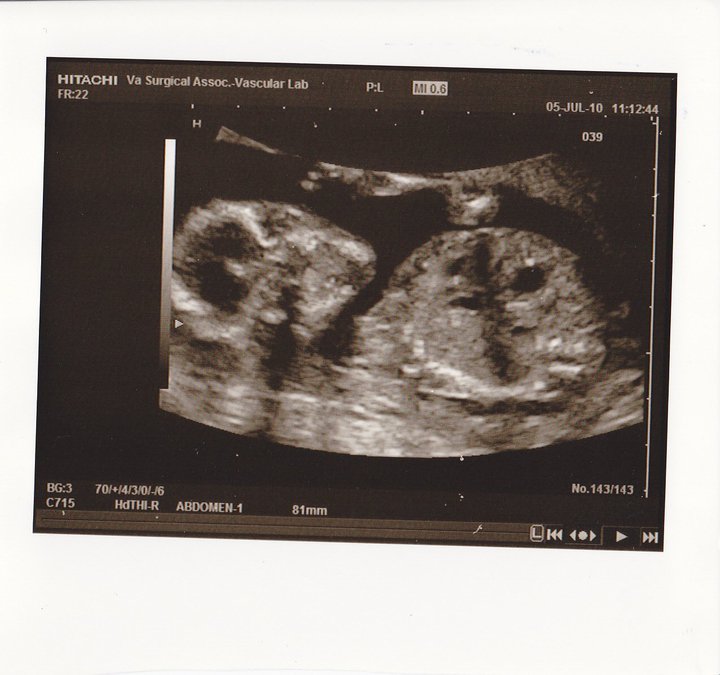

Even though it was a bit early, we were certainly hoping to get a peek at whether Bean is a boy or girl. No such luck... but it was sooo fun to get to see our little one! We haven't seen Bean since 7 weeks. Holy cow, what a CHANGE!! Bean went from being the size of a blueberry to the size of an avocado! And WOW!! Bean waved at us, sucked their thumb, and was doing somersaults! Once as we were peeking at the bum, it disappeared and Bean's face popped up and peeked at us! It was so cute to see those little feet wiggling all over the place. I can't wait to start feeling it! Should be soon. Here's some peeks at our cute Little Bean:

THUMB SUCKER!!!

Hi Mommy & Daddy!!

Cute little profile :)

Spine and heartbeat looked great!